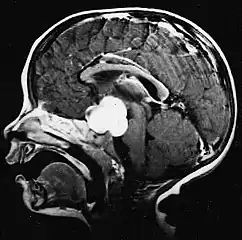

- Sagittal T1-weighted MRI showing a well-circumscribed hypointense mass in the tectum (presumably a tectal plate glioma). These lesions are a distinct subset of pilocytic astrocytoma which present with hydrocephalus typically in 6 to 10 year-olds and are rarely progressive lesions. When imaging is characteristic, a biopsy is usually not performed because of the risks to adjacent structures, often shunting to relieve intracranial pressure is the only treatment required.

- T1-weighted coronal MRI image postcontrast showing heterogeneous contrast enhancement within the presumed tectal plate glioma